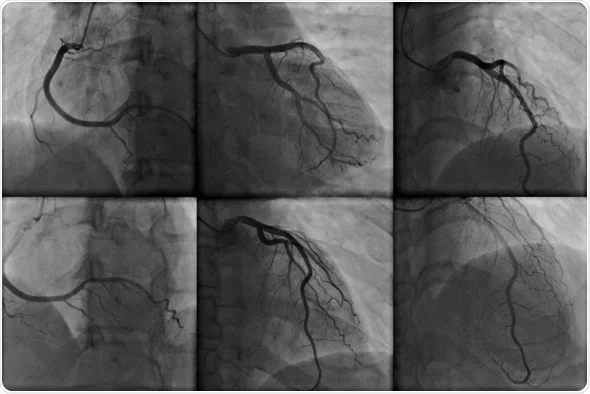

Angiography

- Is a radiographic test used to evaluate blood vessels and the circulation.

- Radiopaque material is injected through a catheter inserted in the blood vessel, and images are recorded using standard radiographic techniques.